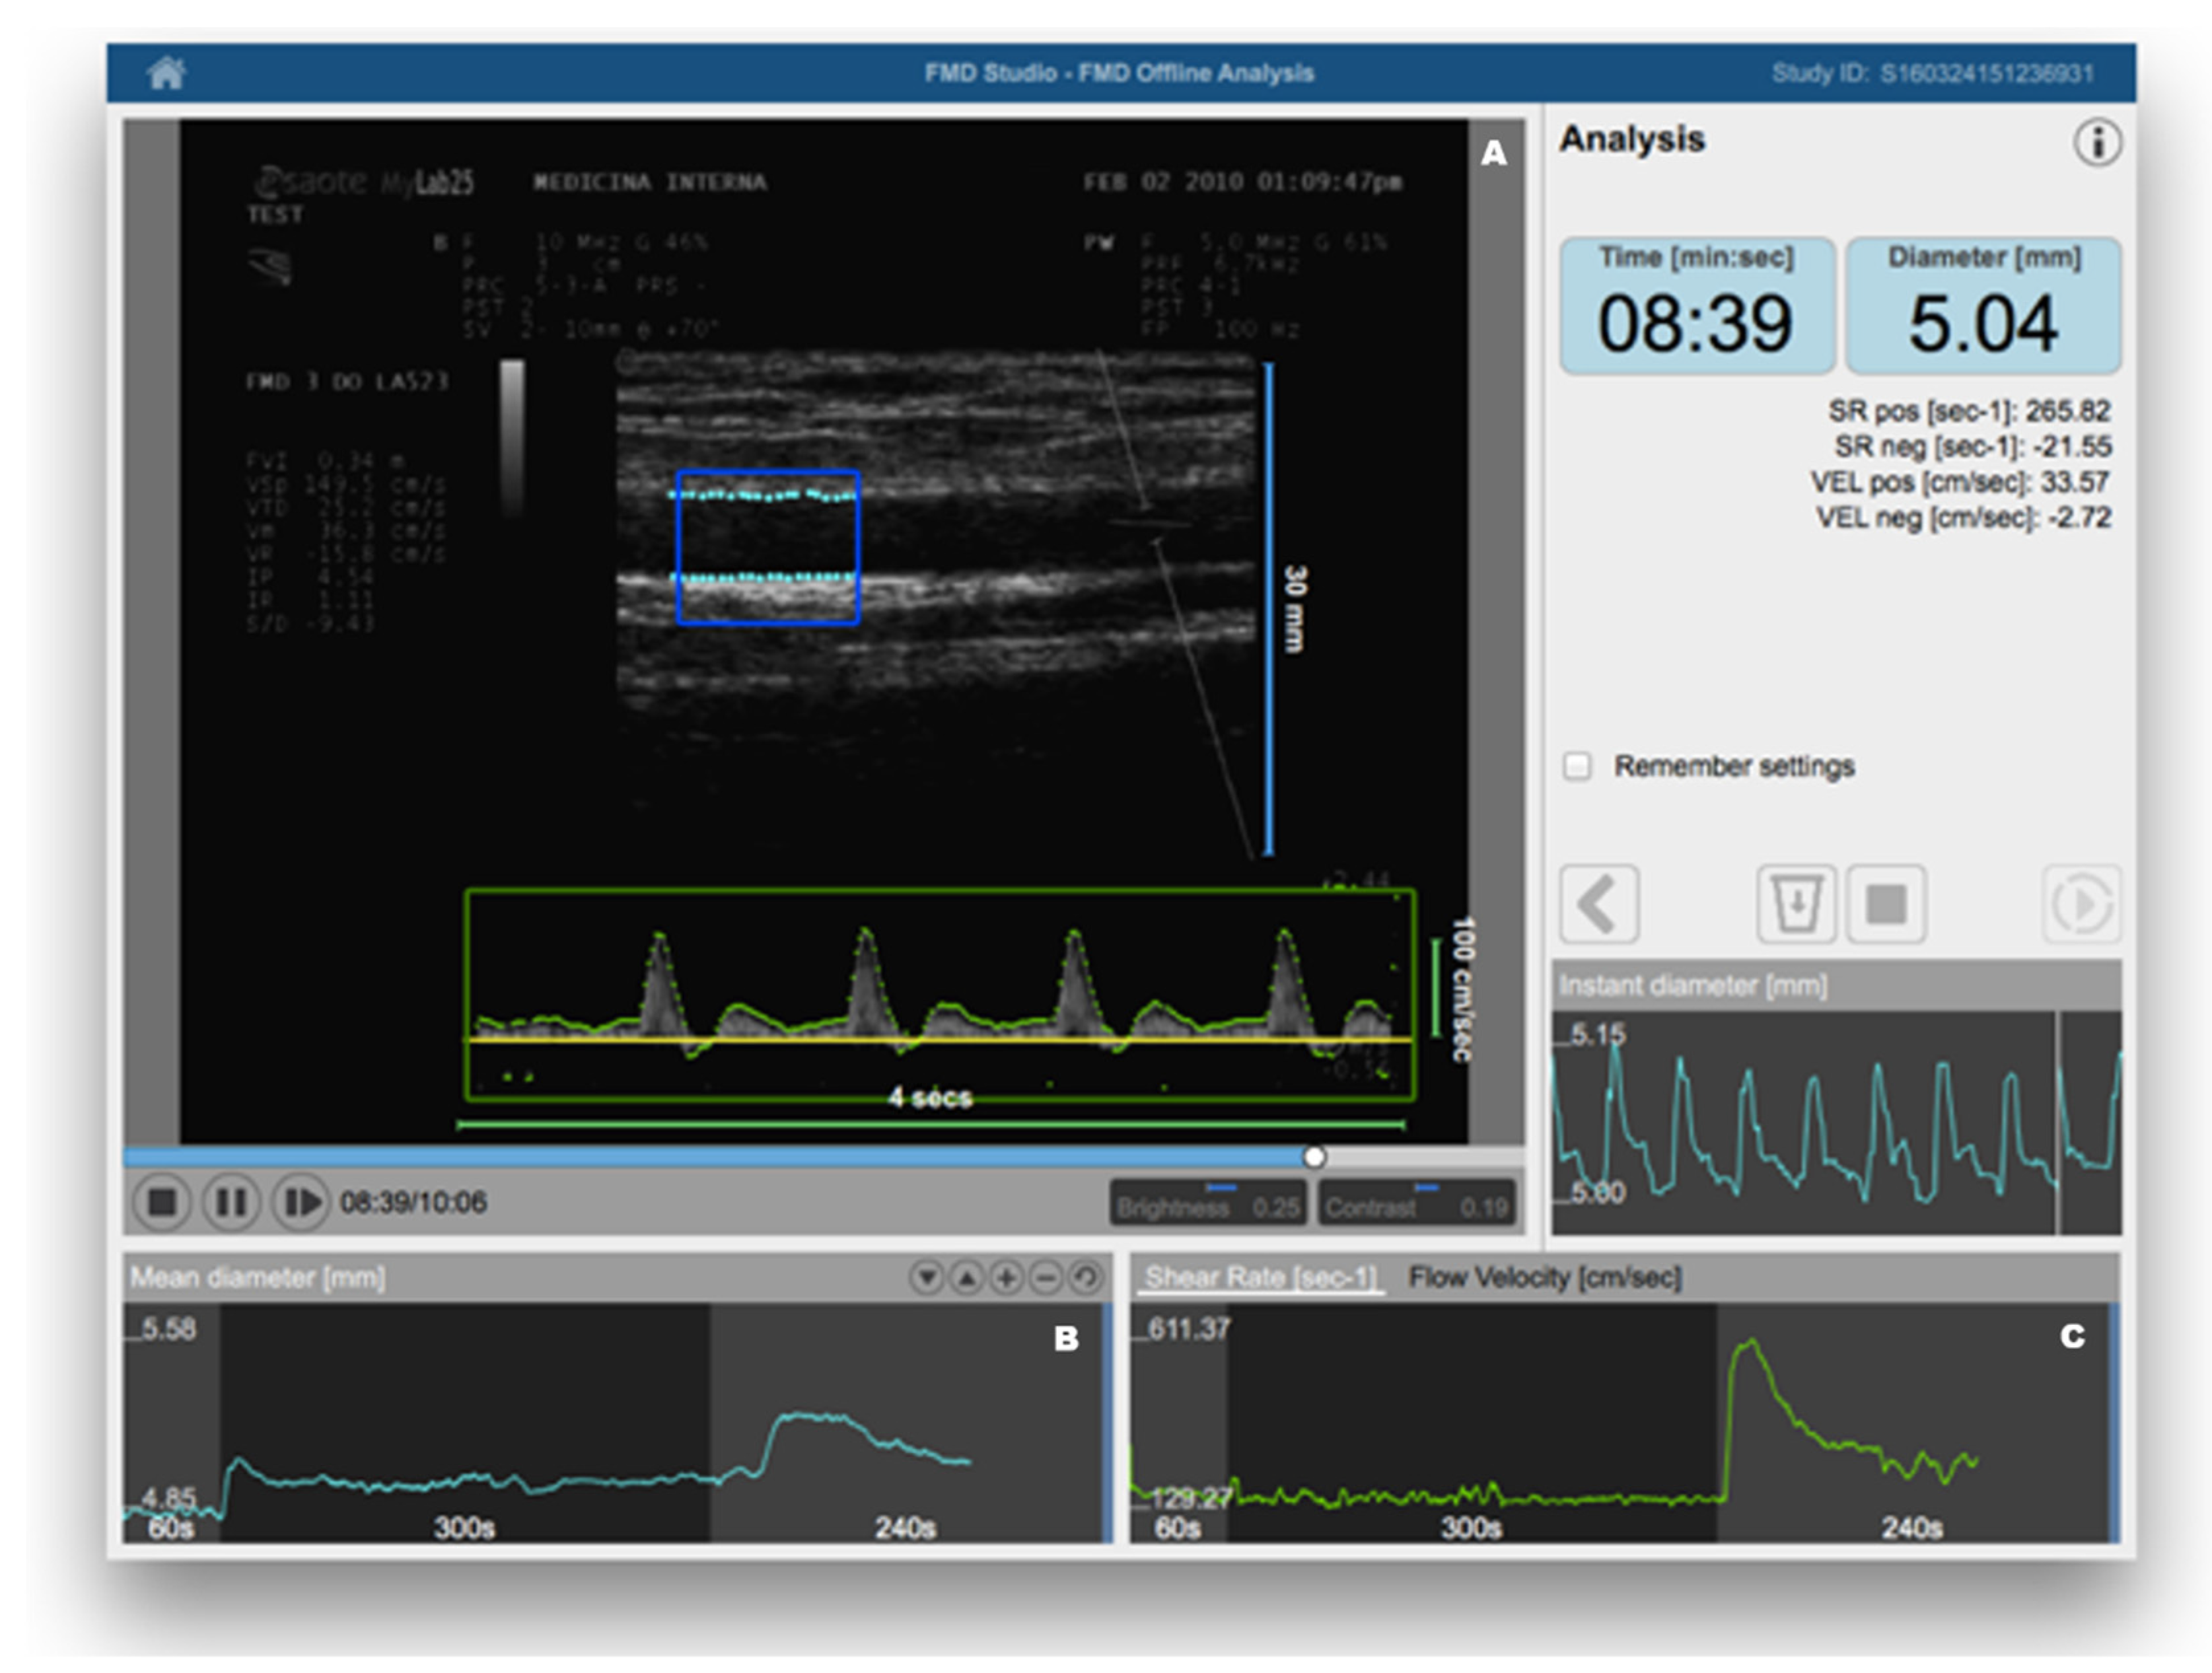

3.1. Clinical Methods

- Thijssen, D.H.; Black, M.A.; Pyke, K.E.; Padilla, J.; Atkinson, G.; Harris, R.A.; Parker, B.; Widlansky, M.E.; Tschakovsky, M.E.; Green, D.J. Assessment of flow-mediated dilation in humans: A methodological and physiological guideline. Am. J. Physiol. Heart Circ. Physiol. 2011, 300, H2–H12. [Google Scholar] [CrossRef] [Green Version]

- Bots, M.L.; Westerink, J.; Rabelink, T.J.; de Koning, E.J. Assessment of flow-mediated vasodilatation (FMD) of the brachial artery: Effects of technical aspects of the FMD measurement on the FMD response. Eur. Heart J. 2005, 26, 363–368. [Google Scholar] [CrossRef]

- Greyling, A.; van Mil, A.C.; Zock, P.L.; Green, D.J.; Ghiadoni, L.; Thijssen, D.H.; Dilation, T.I.W.G.o.F.M. Adherence to guidelines strongly improves reproducibility of brachial artery flow-mediated dilation. Atherosclerosis 2016, 248, 196–202. [Google Scholar] [CrossRef] [PubMed] [Green Version]